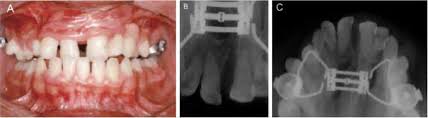

A Expansão Rápida da Maxila é um procedimento ortopédico-ortodôntico destinado a corrigir a deficiência transversal da maxila por meio da abertura controlada da sutura palatina mediana.

Diferentemente das expansões dentoalveolares lentas, a ERM promove uma separação esquelética real, desde que realizada em condições biológicas favoráveis.

Do ponto de vista biomecânico, o princípio da ERM baseia-se na aplicação de forças ortopédicas de alta magnitude e curta duração, capazes de superar a resistência sutural.

Essa força é transmitida por dispositivos expansores fixos, ancorados aos dentes e, em alguns casos, ao palato ou a mini-implantes, promovendo a disjunção da sutura palatina.

O resultado esperado é o aumento da largura transversal do arco superior, acompanhado de alterações secundárias nas estruturas adjacentes, como cavidade nasal, assoalho nasal e arcabouço facial médio.

Tradicionalmente, a Expansão Rápida da Maxila esteve associada ao tratamento de crianças e adolescentes, período em que a sutura palatina mediana apresenta menor grau de interdigitação e maior potencial de resposta ortopédica.

Nessa fase, a expansão tende a ocorrer com maior previsibilidade e menor efeito dentoalveolar indesejado.

Atualmente, a ERM pode ser realizada em adultos por meio de duas principais abordagens:

- Expansão rápida assistida por mini-implantes (MARPE), que direciona as forças de expansão ao osso basal;

- Expansão rápida da maxila cirurgicamente assistida, indicada quando a resistência sutural inviabiliza a expansão ortopédica isolada.

A escolha da técnica deve considerar fatores como idade cronológica, maturação esquelética, espessura óssea palatina, padrão facial e objetivos do tratamento.